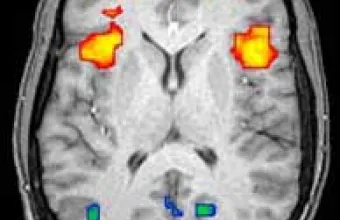

Τι προοιωνίζεται για το μέλλον η αλματώδης πρόοδος των νευροεπιστημών τα τελευταία έτη; Πώς η βαθύτερη κατανόηση του ανθρώπινου εγκεφάλου έχει ευρείες επιπτώσεις και προεκτάσεις, πέρα από την υγεία και την περίθαλψη, στην ίδια την κοινωνία, την τεχνολογία, τη δημόσια πολιτική και τα ανθρώπινα δικαιώματα;

Η συζήτηση επικεντρώθηκε στις ευκαιρίες και τις προκλήσεις που προκύπτουν από την πρόοδο στις νευροεπιστήμες, καθώς και στις επιπτώσεις της πέραν του κλινικού πεδίου. Ιδιαίτερη έμφαση δόθηκε στις προοπτικές ανάπτυξης νέων θεραπειών για νευροεκφυλιστικές ασθένειες και στις προκλήσεις μετάφρασης της έρευνας σε φαρμακευτικές εφαρμογές, καθώς και στις επιδράσεις της νευροεπιστήμης στην τεχνολογία και την καινοτομία, ιδίως σε τομείς όπως η τεχνητή νοημοσύνη. Συζητήθηκαν επίσης ζητήματα όπως τα «νευροδικαιώματα» και η ηθική διάσταση της τεχνολογίας.